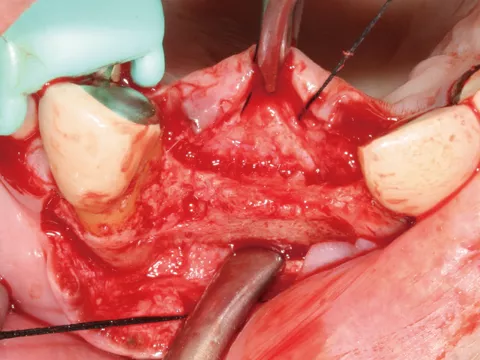

チタンフレーム有。チタン強化型 ‐ リッジオギュメンテーション

臨床動画提供:中田光太郎 先生(京都府開業)

‐チタンフレーム有。チタン強化型‐リッジオギュメンテーション

臨床写真提供:中田光太郎 先生